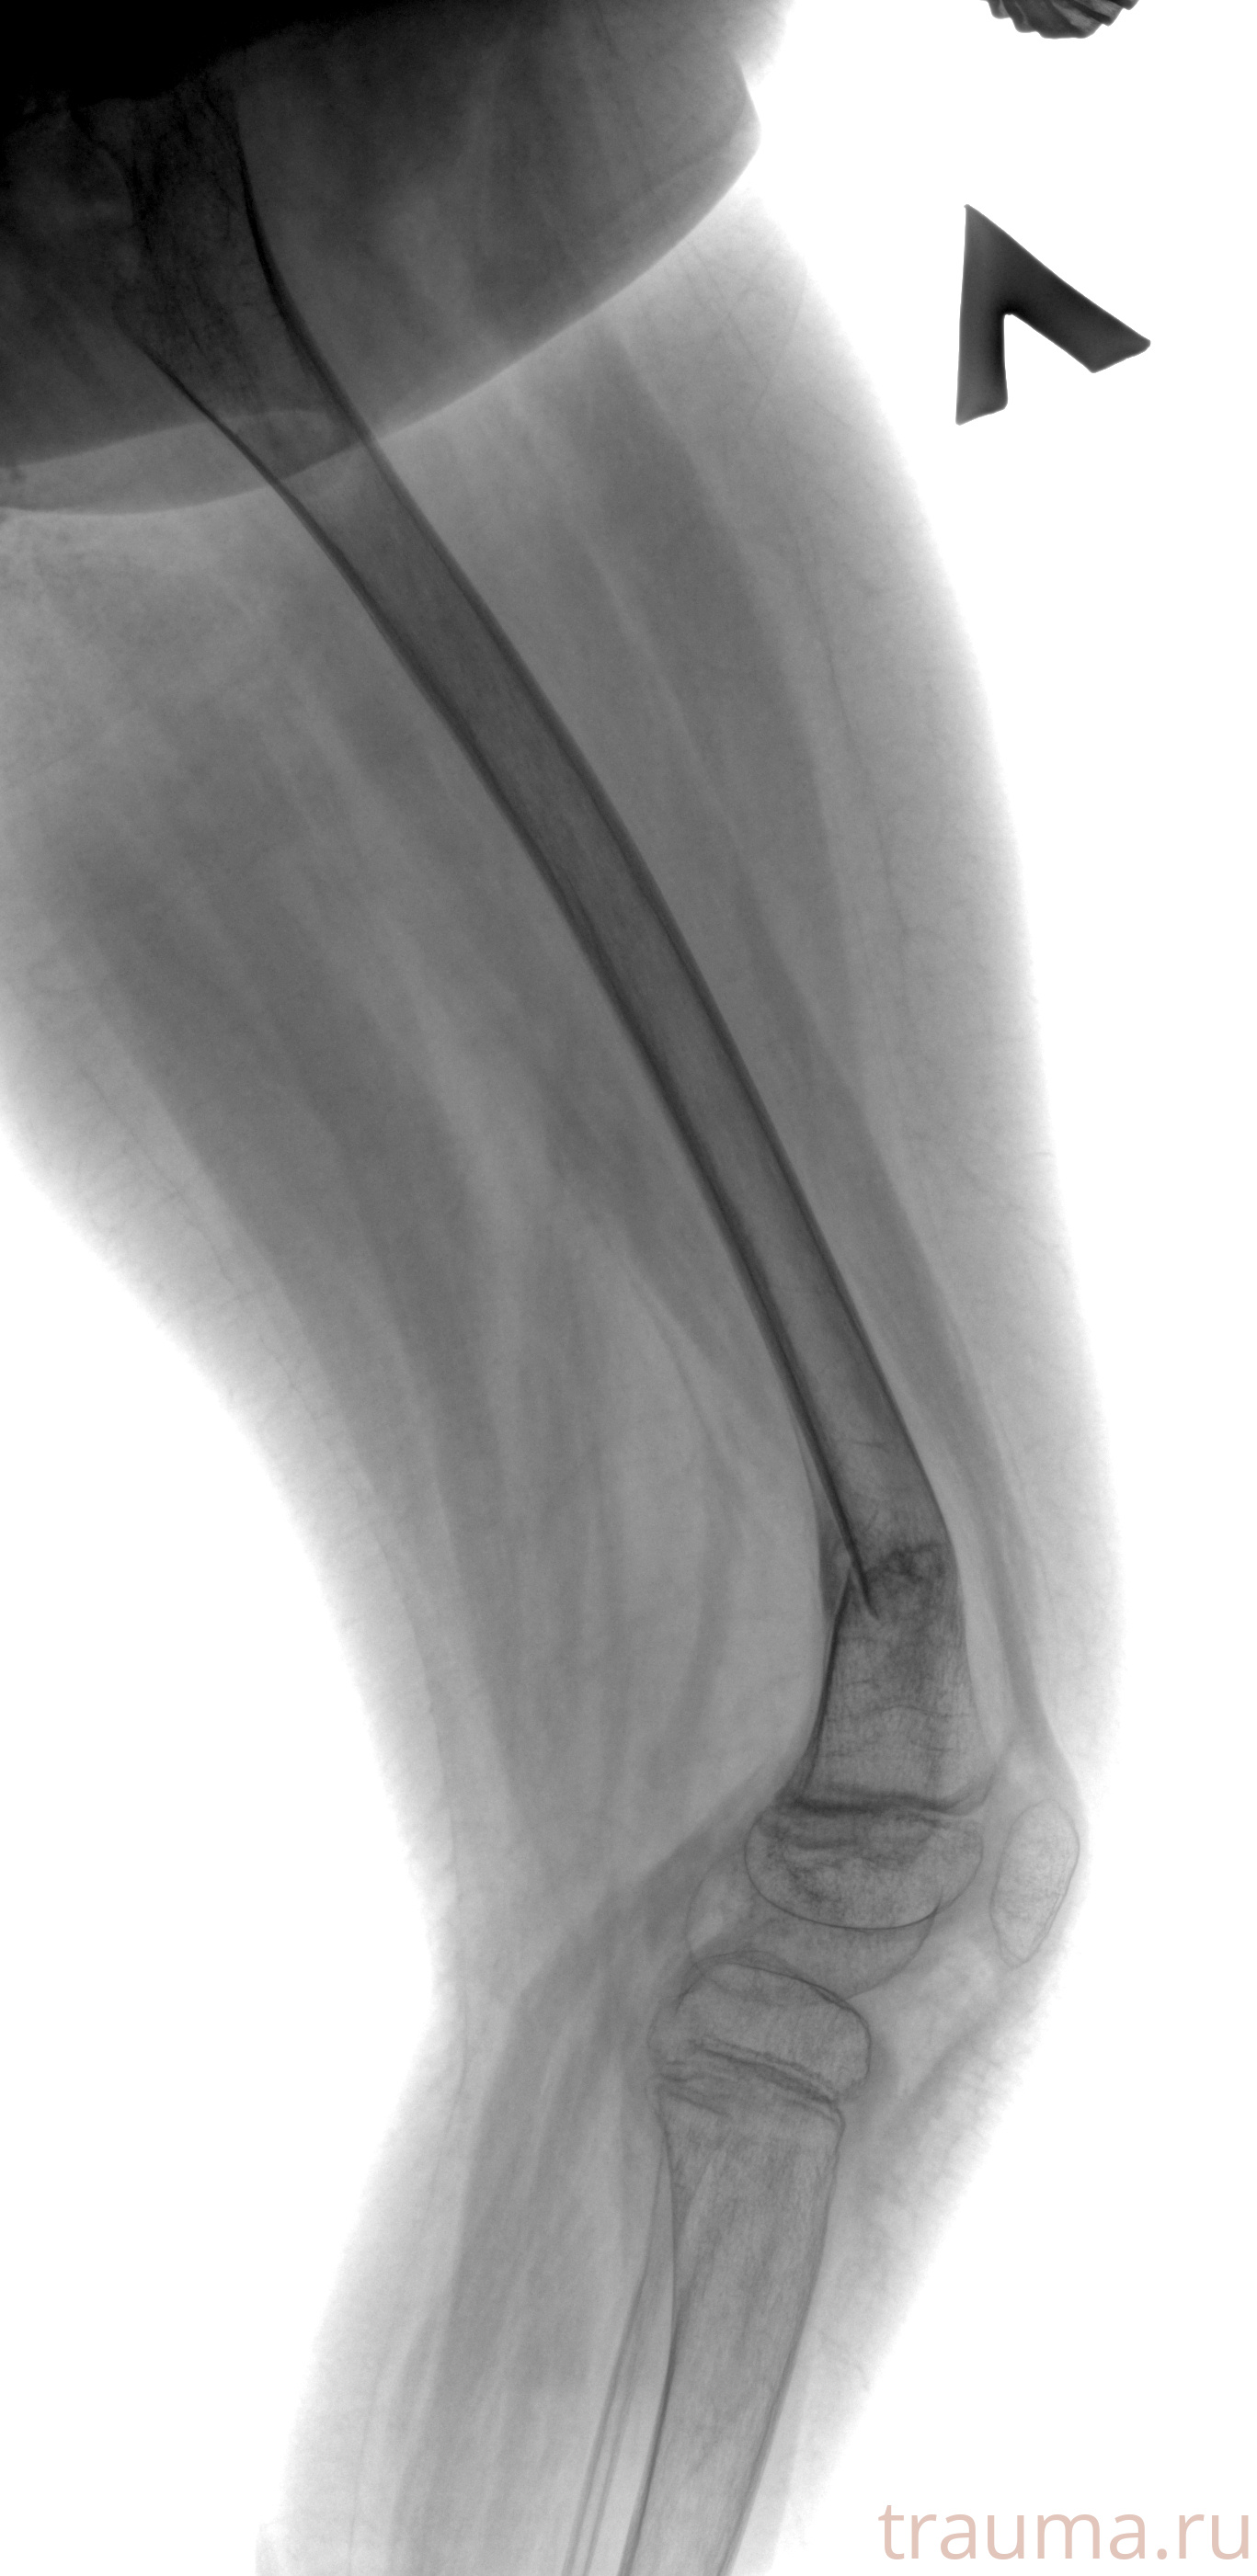

Рентген на дому: по вашему адресу приезжает врач-рентгенолог, травматолог-ортопед с мобильным рентгеновским аппаратом, проводит диагностику травмы или заболевания, делает необходимые рентгенограммы, дает рекомендации по дальнейшему лечению. Получить качественные снимки в домашних условиях возможно благодаря уникальной методике, разработанной МосРентген Центром для института  Склифосовского